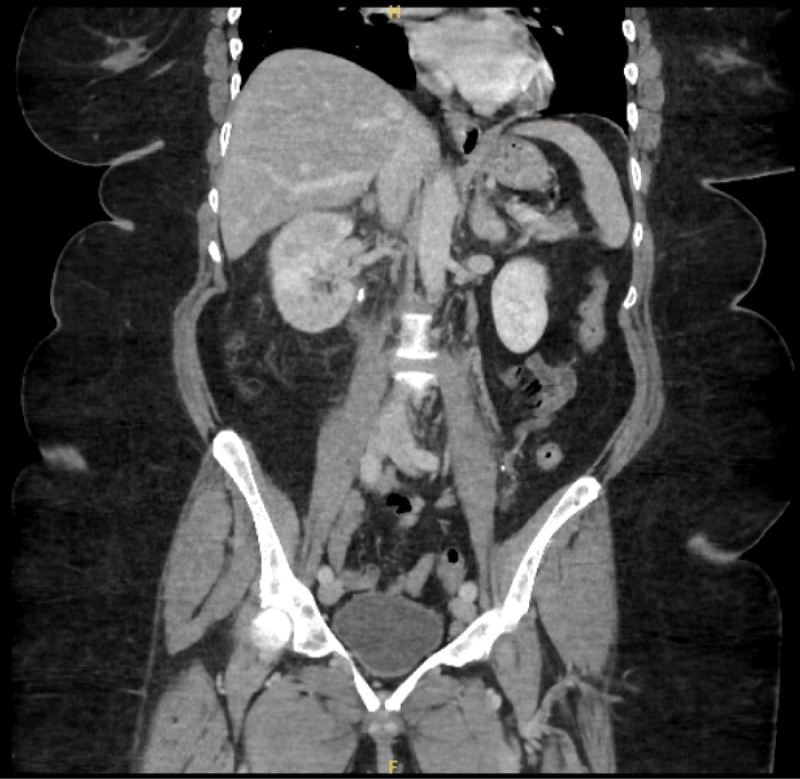

A 64-year-old woman with hypertension and gastroesophageal reflux disease presented with abdominal pain, nausea, vomiting, and fevers for 3 days. On admission, she was tachycardic (HR 110), with blood pressure 133/79 mmHg and temperature 38°C. Laboratory evaluation revealed leukocytosis (WBC 15.5 ×103/µL), lactic acidosis, and thrombocytopenia. Urinalysis was positive for infection with 20 WBC, 10-20 RBCs and Positive Leukocyte Esterase and Nitrites. CT abdomen and pelvis revealed an 8 × 4 mm proximal right ureteral stone with right-sided Uretral Stone and perinephric stranding (Figures 1 and 2).

Figure 2: CT abdomen/pelvis (coronal) demonstrating an 8 × 4 mm right proximal ureteral stone with right-sided hydroureter and perinephric stranding. View Figure 2